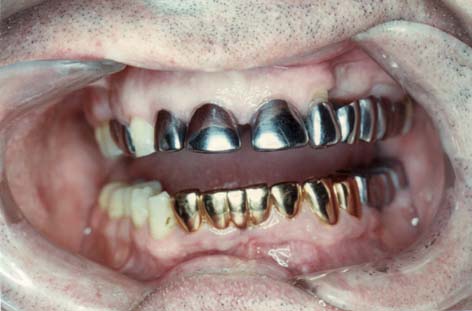

Ein direkter metallischer Kontakt des Amalgams mit einer

Goldrestauration kann Ursache sein für eine zusätzliche

Hg-Exposition von 250 µg täglich (Pleva 1989).